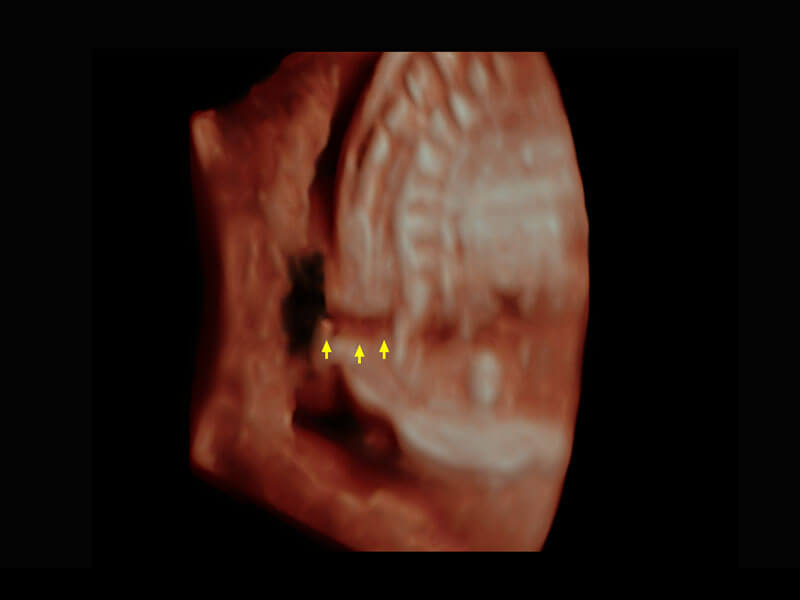

生殖健康

P60优异的图像质量搭载专科探头,在妇科基础疾病的诊断、卵泡生长的监测、输卵管通畅情况的判别等方面为您提供生殖应用方案。

• 腔内妇科-宫腔分离

• 腔内妇科-卵巢

• 腔内三维-宫内节育器

• 腔内三维-光影成像